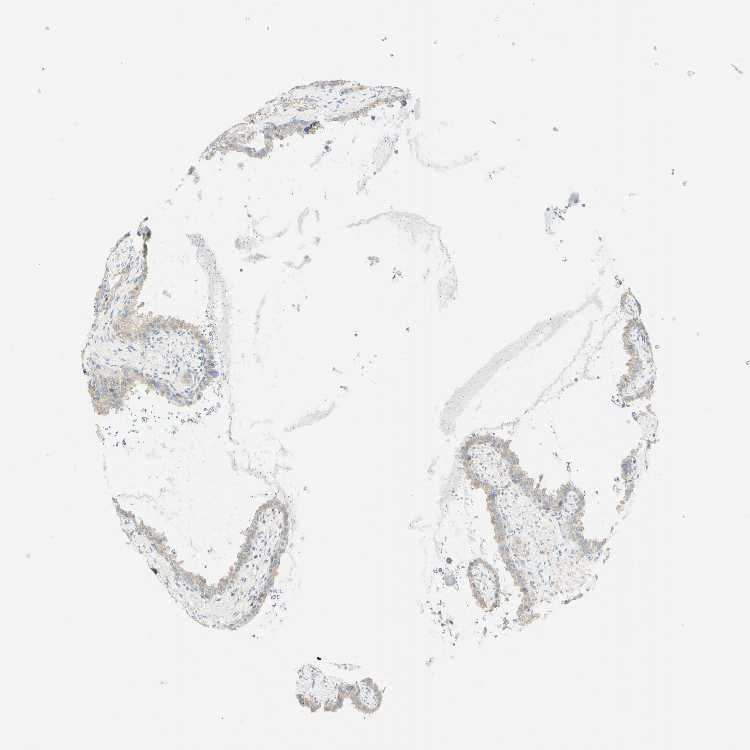

SEMINAL VESICLE - Antibody stainingi

Antibody staining in the annotated cell types in the current human tissue is reported as not detected, low, medium, or high, based on conventional immunohistochemistry profiling in selected tissues. This score is based on the combination of the staining intensity and fraction of stained cells.

Each image is clickable and will lead to virtual microscopy that enables deeper exploration of all samples and also displays staining intensity scores, fraction scores and subcellular localization as well as patient and tissue information for each sample.

Antibody HPA011157Antibody CAB002223Antibody CAB012978Antibody CAB079960

Glandular cells LowNot detectedNot detectedNot detected